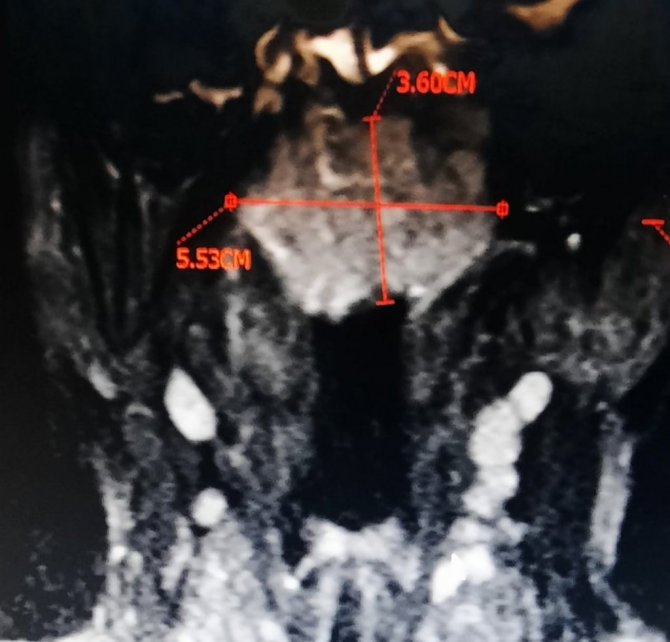

Hastanın yutkunmada dahi zorluk çektiğini ve birçok hastaneye başvurduğunu belirten Dr. Kenar; "Hastalarımızdan bahsedecek olursak, hastamızın biri 80 yaşında burun tıkanıklığı ve yutma güçlüğüyle bize başvurdu. Daha önceki gittiği hastanelerde bir takım tedaviler almış ama şikayetleri geçmeyince bize başvurduğunda, ileri yaştaki hastamızın burun tıkanıklığı şikayetine yönelik ilk etapta endoskopi ile baktık ve genzinde büyük bir kitle gördük. Genzini tamamen tıkayan, yutkunmasını dahi zorlaştıran tümör kitlesini kapalı (endoskopik) burun ameliyatıyla olabildiğince küçültüp aldık, patolojiye yolladık. İncelemeler sonucunda geniz kanseri teşhisi konuldu. Hastamız halen kemoterapi ve radyoterapi ile tedavisine devam etmektedir" ifadelerini kullandı.

Bu kanserin yaş fark etmeksizin her grupta görülebileceğini belirten Dr. Kenar; "Diğer hastamızın yaşı nispeten küçük ,16 yaşında. Bu hastamız bize tek taraflı işitme kaybı ile başvurdu. Burada bir kez tedavi verdik, normalde iyileşmesi lazım o yaşlarda işitme kaybının tedaviyle, ancak hastamızın şikayetinde hiçbir düzelme olmayınca, olası bir geniz eti varlığı için, ucu ışıklı kamerayla geniz muayenesi yaptığımızda genzinde özellikle sol tarafı tıkayan bir kitle gördük. Bu kitleyi tama yakın olabildiğince çıkarıp açıklığını sağladık. Hem de östaki borusu açıldı, kulağı havalanmaya başladı. Aynı seansta kulağına havalandırma tüpü de taktık. Gönderdiğimiz parçanın patolojisi geniz kanseri çıkması sonucunda da hastamıza kemoterapi ve radyoterapi almak üzere Onkoloji Bölümüne yönlendirdik. Şu anda hastalarımız tedavilerine başladılar. Geniz kanseri açısından uyanık olmak, şüphelenmek ve gerekli muayeneleri yapmak üzere kulak burun boğaz hekimine başvurmakta fayda olacağını düşünüyorum" şeklinde konuştu.